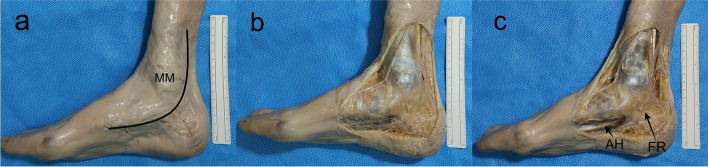

Methods: The distal part of the legs, ankles and feet of 12 Thiel embalmed cadavers were dissected. The pattern of the branches of the TN was registered and the measurements were performed according to the Dellon-McKinnon malleolar-calcaneal line (DML) and the Heimkes Triangle (HT).

Results: The TN divided proximal to DML in 87.5%, on top of the DML in 12,5% and distal in none of the feet. The Baxter's nerve (BN) originated proximally in 50%, on top of the DML in 12,5% and distally in 37.5% of the cases. There was a strong and significant correlation between the length of DML and the distance from the center of the medial malleolus (MM) to the lateral plantar nerve (LPN), medial plantar (MPN) nerve, BN and Medial Calcaneal Nerve (MCN) (ρ: 0.910, 0.866, 0.970 and 0.762 respectively, p <  0.001).